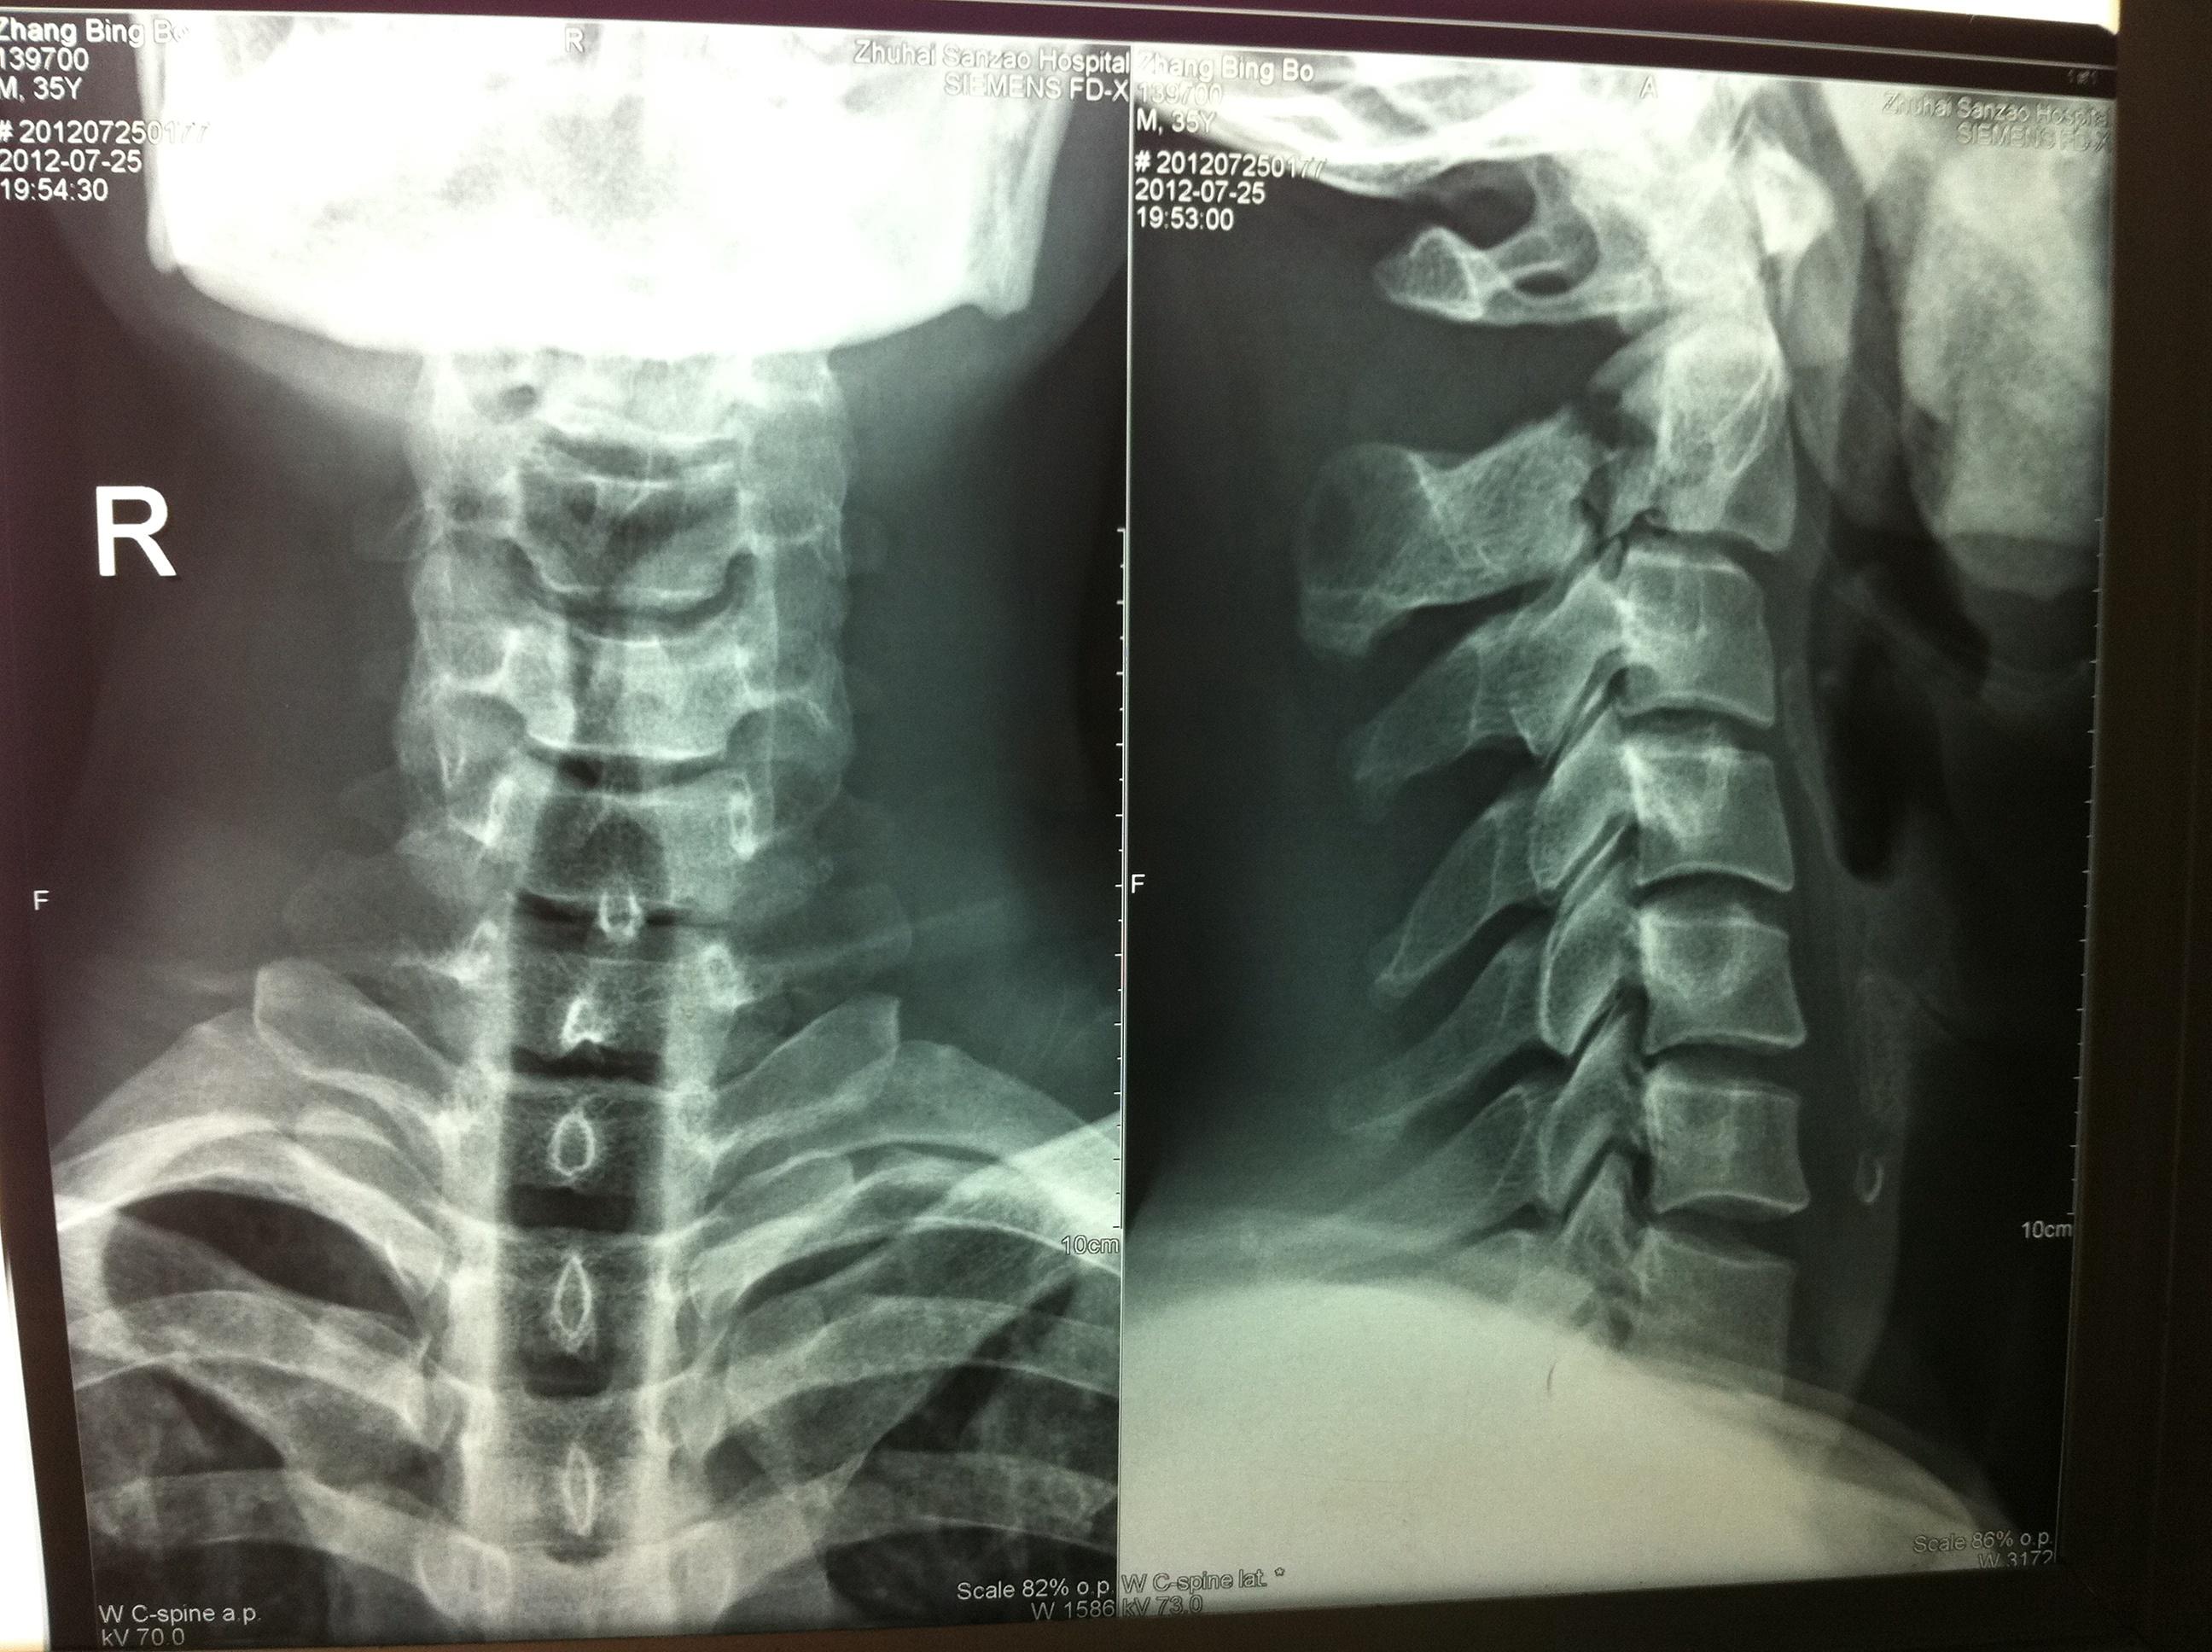

颈椎正侧位x线显示枢椎椎弓骨折,枢椎椎体后下缘骨折,系过伸损伤所致